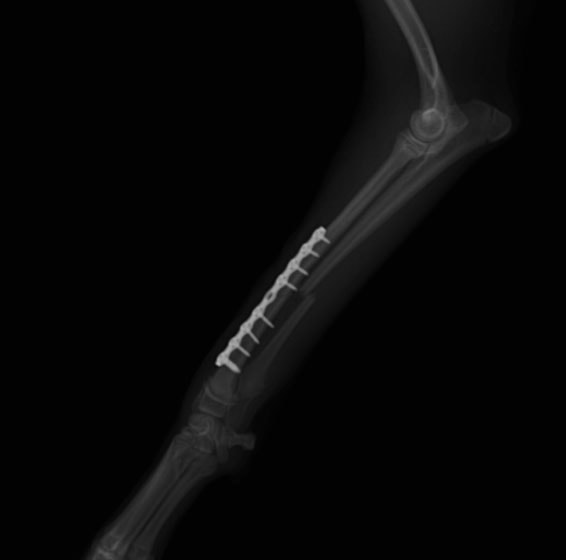

トイプードル 右遠位橈尺骨短斜骨折のALPSによる内固定

Locking Compression Plate

LCPは、スクリュー(ネジ)とプレート(金属の板)をロックする特殊な構造により骨折部位を固定する新しい世代のプレートシステムです。ひとつのホールでロッキングスクリューとスタンダードスクリューの使用を選択できるユニークな構造をしているため、骨折断端間の圧迫を目的とした従来型プレート固定法に加え、高い角度安定性を有するロッキングスクリューを用いた固定法の選択が可能です。従来のプレートシステムでは困難だった部分の骨折や癒合不全の症例に高い治療効果をもたらします。